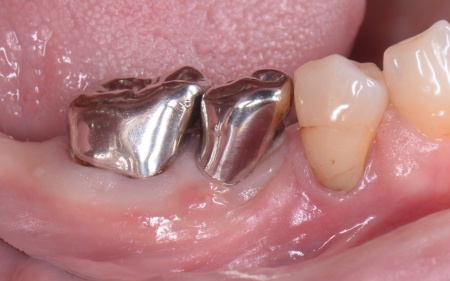

3ヶ月後、インプラントと骨がしっかりと結合したことが確認できたため、被せ物を作製するための型取りを行います。

被せ物には、人工ダイヤモンドと呼ばれるほど高い強度をもつ、ジルコニアセラミックを使用したブリッジを製作しました。

後日、完成した被せ物を装着し、見た目や噛み合わせに問題がないことを確認して、治療を終了しています。